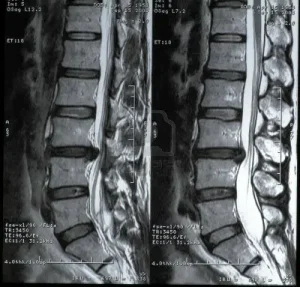

- MRI (Manyetik Rezonans Görüntüleme): Fıtıklaşmış diskin ve sinirlerin detaylı bir şekilde görüntülenmesini sağlar.